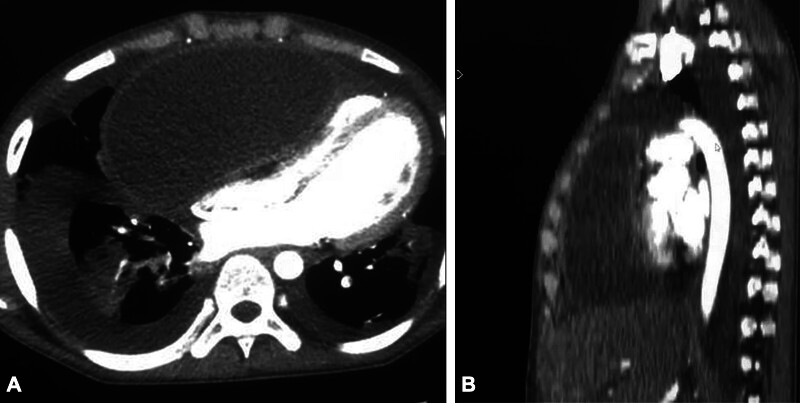

胸膜心包囊肿是一种罕见的纵隔肿瘤,临床表现多变,常为严重的儿童,偶尔需要紧急干预。我们报告的情况下,以前健康的14岁男性谁是入院严重充血性心力衰竭的迹象和心脏填塞的临床证据。经胸超声心动图和胸部CT扫描证实存在压缩纵隔囊性肿块。患者经胸骨正中切开术行紧急手术切除。组织病理学检查证实为良性心包囊肿。术后恢复平稳,随访2年无复发。

Pleuropericardial cysts are rare mediastinal tumors with variable, often severe, clinical presentations in children, occasionally requiring urgent intervention. We report the case of a previously healthy 14-year-old male who was admitted with signs of severe congestive heart failure and clinical evidence of cardiac tamponade. Transthoracic echocardiography and thoracic CT scan confirmed the presence of a compressive mediastinal cystic mass. The patient underwent emergency surgical resection via median sternotomy. Histopathological examination confirmed a benign pericardial cyst. Postoperative recovery was uneventful, and no recurrence was observed after 2 years of follow-up.